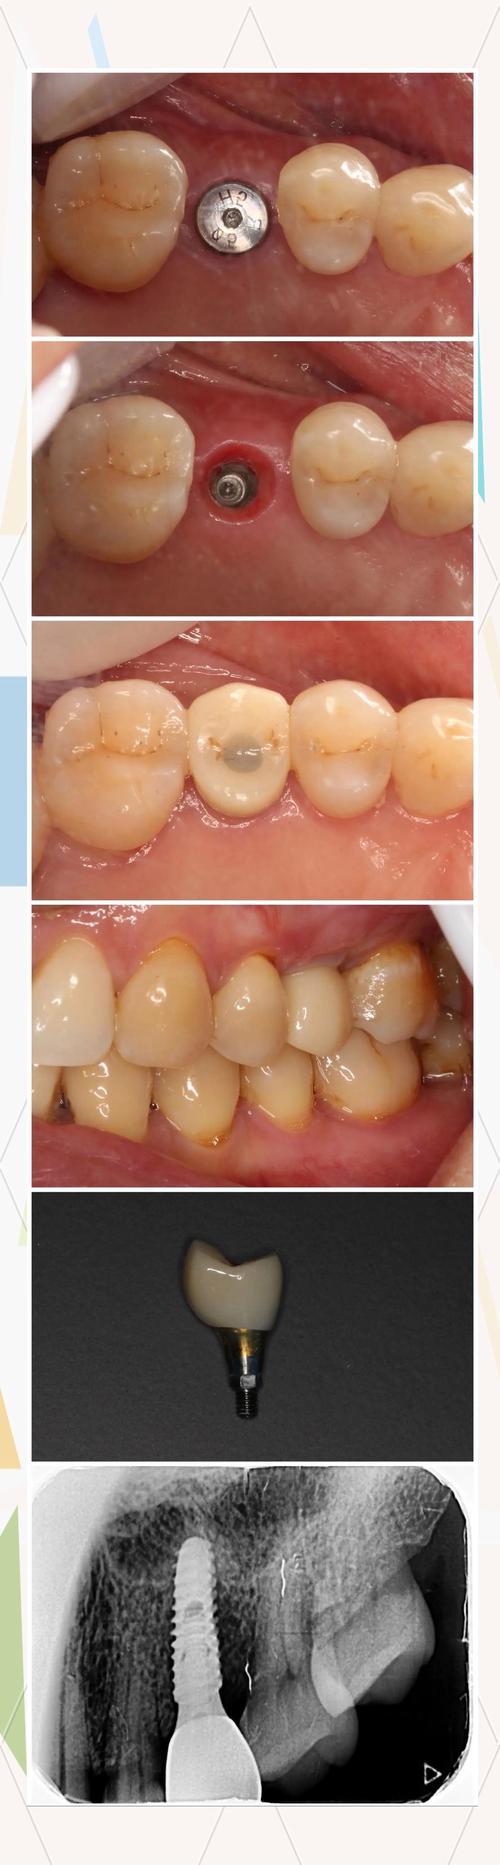

种牙植骨粉后照片是记录治疗过程、评估恢复情况的重要依据,既能帮助医生动态观察骨结合与软组织愈合状态,也能让患者直观了解自身恢复进展,这类照片通常涵盖术后即刻、拆线时、术后3个月、6个月及1年等多个时间节点,每个阶段的照片重点不同,共同构成了完整的恢复轨迹。

术后3个月 需结合口内照片与X光片(根尖片或CBCT),口内照片观察牙龈形态是否饱满、有无萎缩;X光片重点查看植骨区域骨密度是否均匀、种植体周围是否有透射影(提示骨结合不良)。

核心意义:3个月是植骨材料初步完成骨结合的关键时期,此时骨组织逐渐被新生骨替代,X光片上可见植骨区域与种植体界面模糊,密度接近自体骨;口内照片则显示牙龈色泽正常,无塌陷,为后续二期手术(安装愈合基台)提供依据。

术后6个月 口内照片关注牙龈乳头形态、种植体周围牙龈宽度及稳定性;X光片评估骨结合程度,测量种植体周围骨吸收情况(正常应<1.5mm)。

核心意义:6个月时种植体应达到稳定的骨结合,牙龈形态逐渐接近自然牙,此阶段照片可判断是否进入修复阶段(安装牙冠),若牙龈形态不佳(如牙龈乳头缺失),可能需进行牙龈修整;若X光片显示骨吸收明显,则需延长愈合时间或调整修复方案。

术后1年及 annually(每年复查) 口内照片观察牙冠与牙龈的协调性、咬合接触情况;X光片监测种植体周围骨密度及骨吸收进展。

核心意义:长期随访照片是评估种植体成功率的重要指标,正常情况下,种植体周围骨吸收应趋于稳定,每年<0.2mm;牙龈无红肿、退缩,牙冠无松动或崩裂,说明种植功能良好。